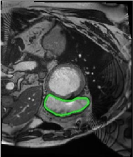

From the above discussions, we have discovered the significant potential of applying Retinex theory to image segmentation and explored its fundamental differences from traditional models. Traditional image segmentation models typically focus on the impact of intensity information on the segmentation results. Therefore, when faced with complex segmentation scenarios, the segmentation results are often affected by lighting, artifacts, and unclear boundaries in the image. As shown in Fig. 1, we present the results of the classical local model LIF [ZHANG20101199] for segmenting brain tumor images along with surrounding tissue edema. The irregular ring-like enhancement caused by the edematous tissue leads to irregular boundaries and low contrast in the images. Consequently, the LIF model can only identify the central necrotic and liquefied regions of the tumor, failing to detect the boundaries and becoming trapped in local minima. In this paper, we draw inspiration from the Retinex theory, which is widely applied in the field of image enhancement. According to Retinex theory, the reflectance component characterizes the intrinsic structural properties of the observed image and preserves texture information independent of illumination variations. By integrating this reflectance component into the level set framework, our model achieves robust segmentation of medical images even under severe intensity inhomogeneity. In addition, a linearized Structural-Prior is proposed to restore intensity consistency and capture local geometric features, thereby improving boundary localization in complex or blurred regions. Furthermore, a relaxed binary level set representation is employed to enhance robustness against noise and to enable accurate tracking of complex contours. Based on these innovations, we propose a novel variational reflectance-based level set model (RefLSM) that simultaneously corrects bias fields and performs segmentation. Experimental results demonstrate that RefLSM significantly outperforms conventional level set methods in both segmentation accuracy and robustness. We present the results of our model segmenting the two brain tumor images mentioned above in Fig. 2.

To address the challenge of segmenting images with severe intensity inhomogeneity, we propose a linearized structural prior that directly operates on the reflectance component . Reflectance-based structural information is more robust to illumination variations and bias field distortions, helping preserve weak edges and subtle anatomical boundaries. As shown in Fig. 2, our method can accurately delineate tumor boundaries and surrounding edema even under severe inhomogeneity, where traditional intensity-based models often fail. The proposed prior aligns smoothed reflectance gradients with data-driven directions, enhancing inter-region contrast, preserving weak edges, and stabilizing the evolution of . Formally, we define the linear structure operator as the gradient field of the smoothed reflectance: